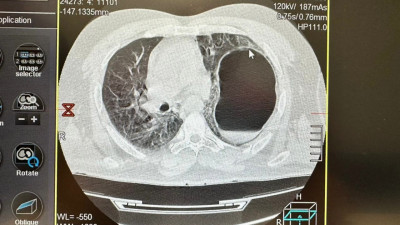

Врачи Истринской больницы оказали экстренную помощь 45-летнему мужчине, у которого после падения с высоты произошло смещение органов. Пациент с трудом дышал и не мог двигаться.